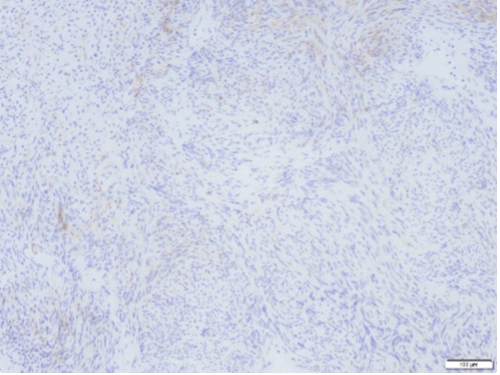

S-100 positivity on immunohistochemical staining confirms diagnosis of gastric schwannoma